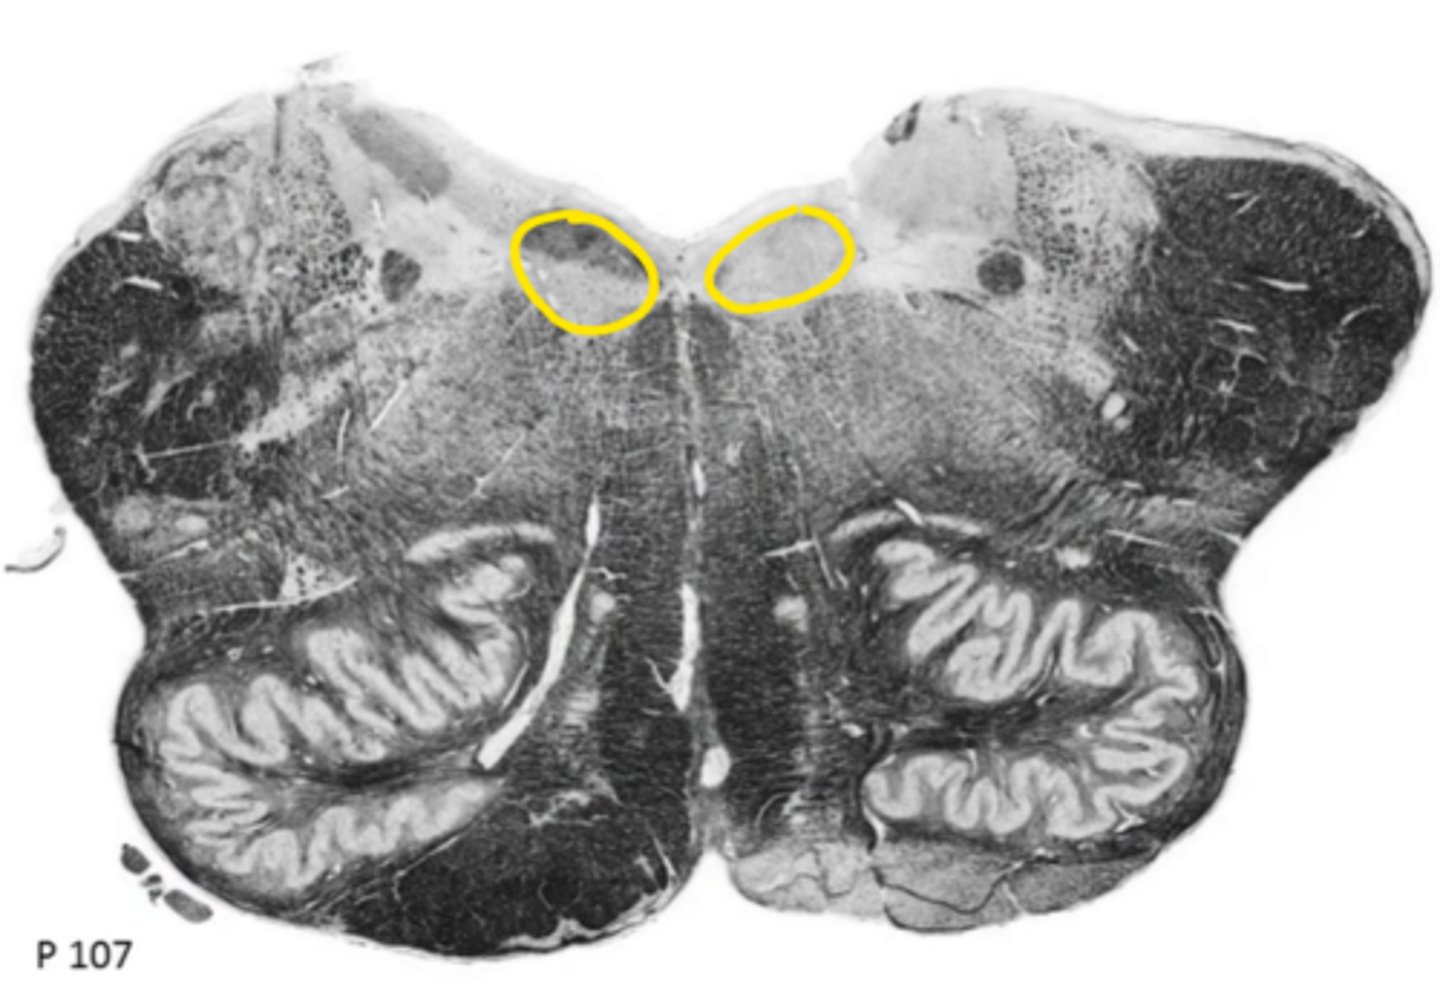

fourth ventricle

ID the space

hypoglossal nucleus

ID the nucleus

vestibular nucleus